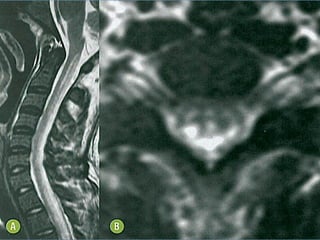

ACHADOS DE IMAGEM

RM de Crânio + Cervical + Torácica

• T1:

 Discreto espessamento da medula espinal sem

evidência de alteração de sinal ou impregnação

pelo contraste;

• T2:

– Hiperssinal linear contínuo e simétrico dos

funículos posteriores e laterais. Não é

necessário o achado combinado.

• Hiperssinal em T2/FLAIR da região bulbar posterior,

por extensão espinal no fascículo gracil e cuneiforme;

• Hiperssinal T2/FLAIR em substância branca

subcortical difuso e assimétrico;

Explica a depressão e déficit

cognitivo?